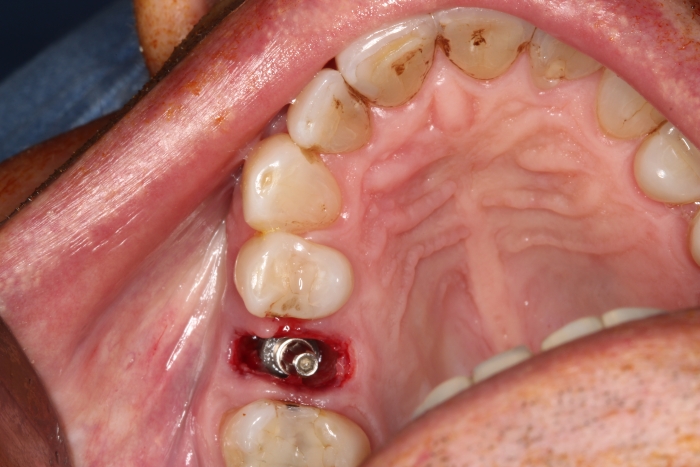

Extração - Implante imediato

Implante - Enxerto ósseo sintético